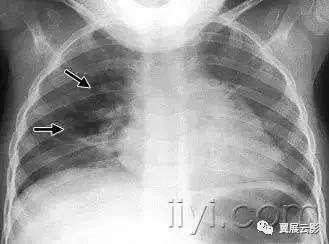

三十、间质性肺气肿

病理:间质性肺气肿的特征是气体位于肺间质之内,尤其是在支气管血管束鞘内,小叶间裂内和脏层胸膜内。最常见于机械通气的新生儿。

平片和CT:成人胸片少见间质性肺气肿,在CT扫描上偶尔可以见到。表现为血管周围透亮影或者低密度晕征和小囊肿。